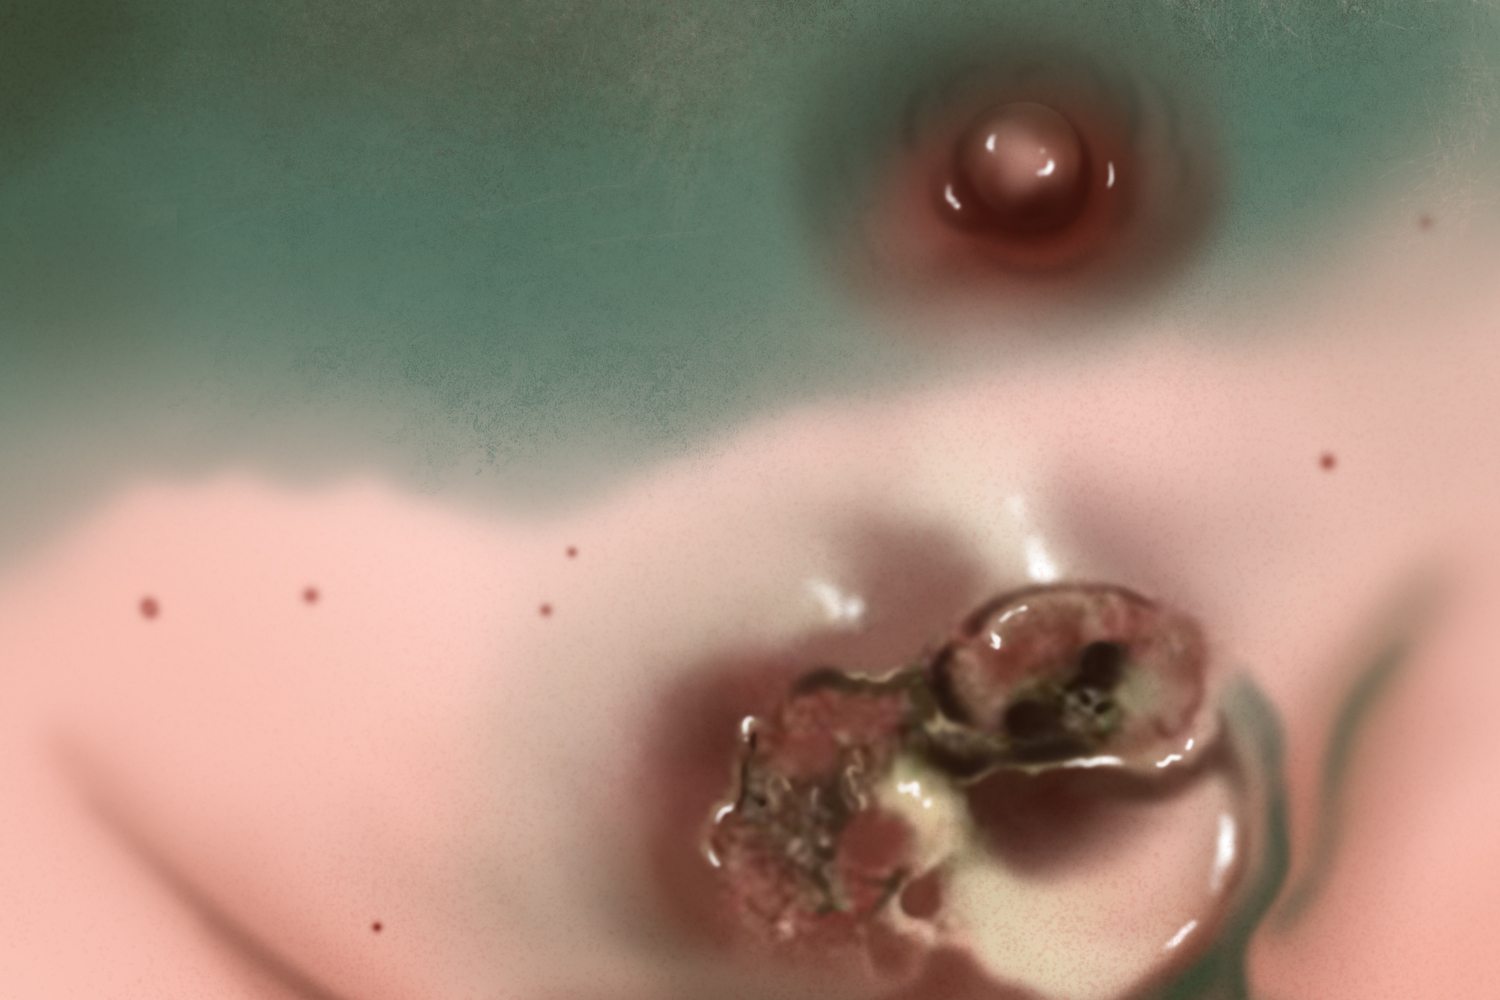

乳腺癌发展至晚期,可侵入胸肌筋膜、胸肌,以致肿瘤固定于胸壁而不易推动。如癌细胞侵入大片皮肤,可出现多个小结节,甚至彼此融合。有时皮肤可溃破而形成溃疡,这种溃疡常有恶臭,容易出血,从而出现乳腺癌结痂溃烂的情况。